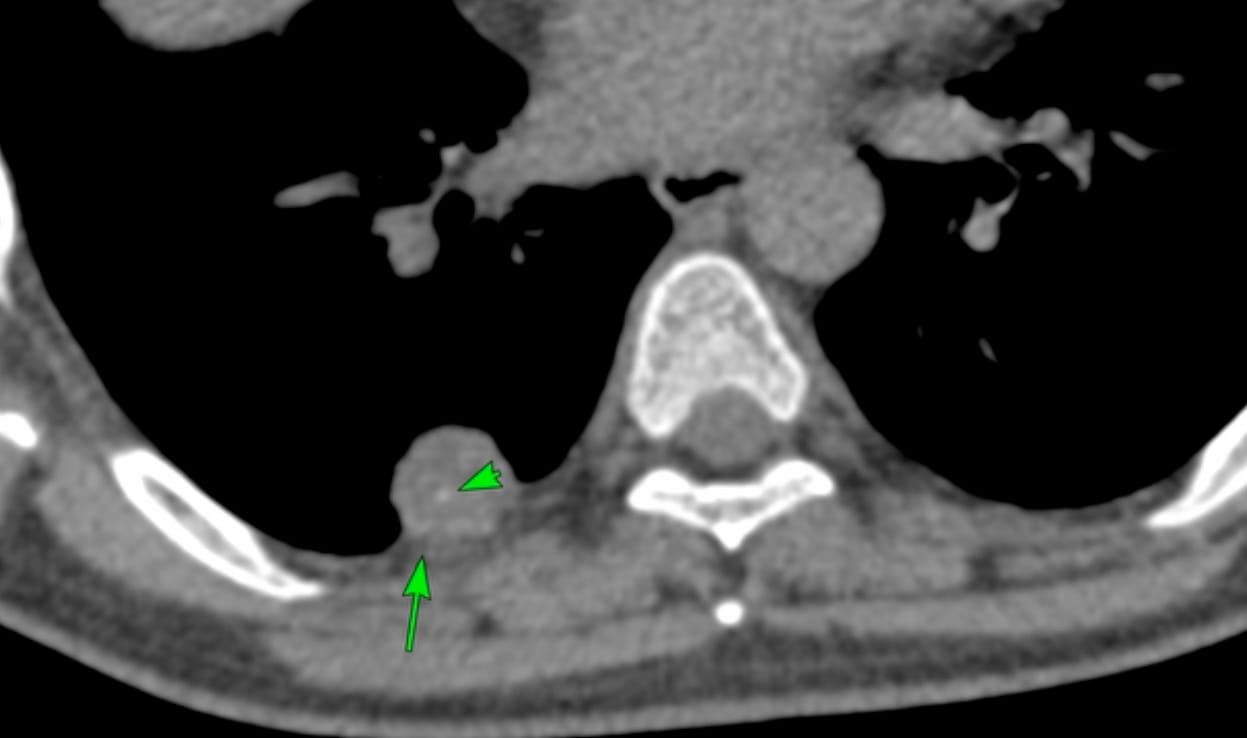

The PDIF sign is basically the presence of a fibrosing ILD typically compacted within the last 2 cm of the peridiaphragmatic lung and may suggest not just CTD-ILD but specifically myositis ILD